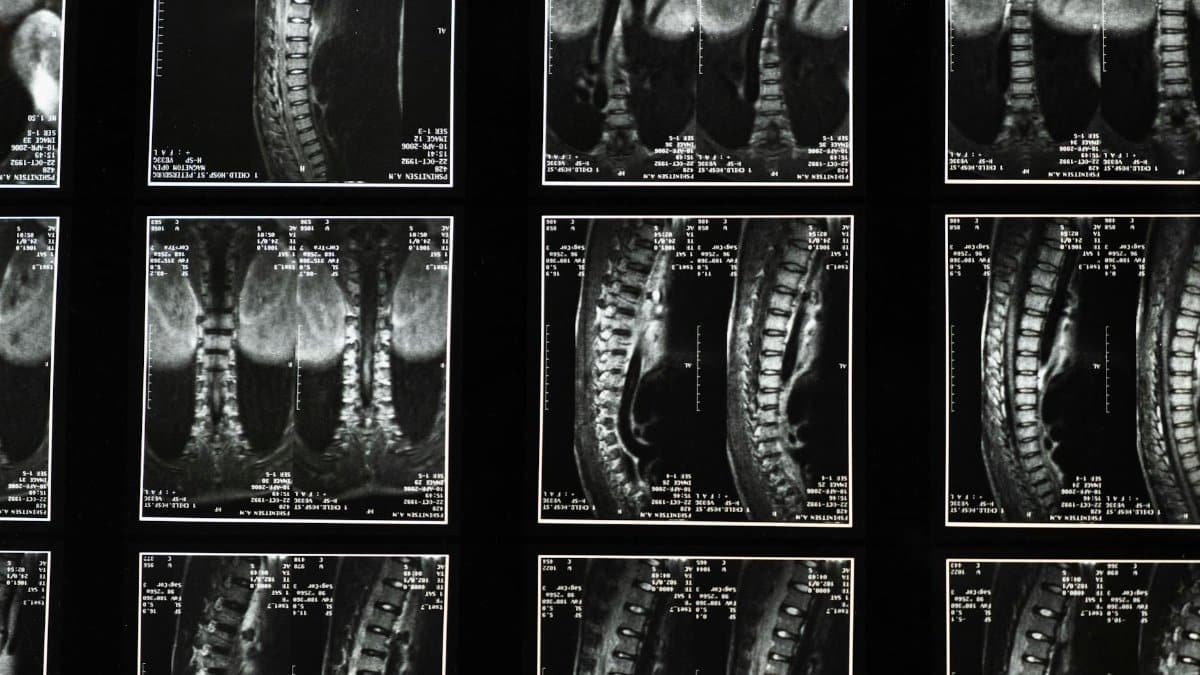

Unpacking the Spinal Stroke

A spinal stroke disrupts blood flow to the spinal cord, a rare occurrence compared to brain strokes. Aaron’s case highlights its stealthy onset. Symptoms mimic other emergencies, leading to the initial confusion. Medical experts note these events stem from blockages or bleeds in spinal arteries, causing sudden weakness or collapse. Aaron’s experience embodies this unpredictability, making his story a cautionary reference.

Medical Context and Resources

Health professionals emphasize spinal cord infarction—another term for spinal stroke—as a vascular emergency. For deeper insight, resources outline symptoms like abrupt paralysis or pain. Aaron’s collapse aligns with classic presentations. In the U.S., improved imaging aids detection, yet rarity delays awareness. Check Mayo Clinic on spinal stroke for reliable details. Similarly, the MedlinePlus entry on spinal cord infarction covers causes and outlook, grounding public knowledge.